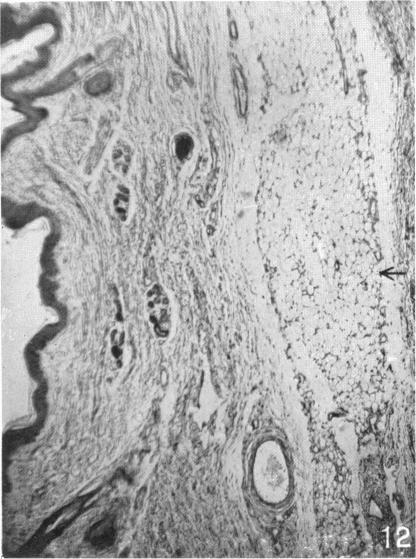

The So-called Interscapular Gland and Tumours Arising Therein.